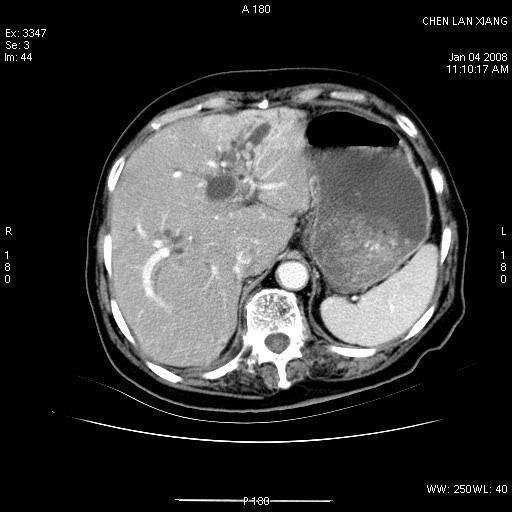

女,76岁,腹痛3-4天,b超示:肝内实性肿物,胆囊强回声,胆总管扩张.

考虑:1、胆总管下端结石伴梗阻性肝内外胆管扩张(肝左叶外侧段肝内胆管多发结石、胆管炎);

2、肿囊癌累及肝,不除外 黄色肉芽肿性胆囊炎。

1 胆总管末端结石伴肝内胆管结石,肝内外胆管扩张。2 胆囊扩大,胆囊壁不规则增厚,内见软组织密度影。考虑:慢性胆囊炎,不除外胆囊癌!

标题: 肝右叶病灶

胆囊癌侵犯肝右叶?

1)胆囊癌伴肝脏转移。2)胆总管下端结石、肝内胆管结石伴肝内外胆管扩张。